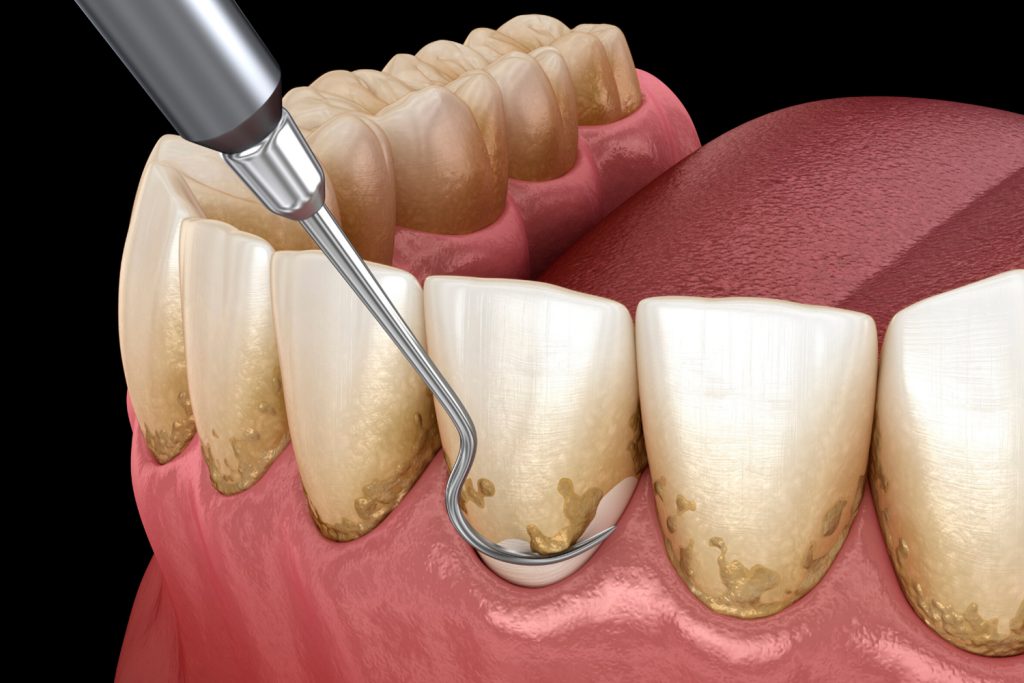

Nos enfocamos en una atención integral de tu tratamiento, por ello contamos con especialistas en Periodoncia (para atender correctamente tus encías) Endodoncia (tratamientos de conductos) Ortodoncia (para alinear tus dientes).